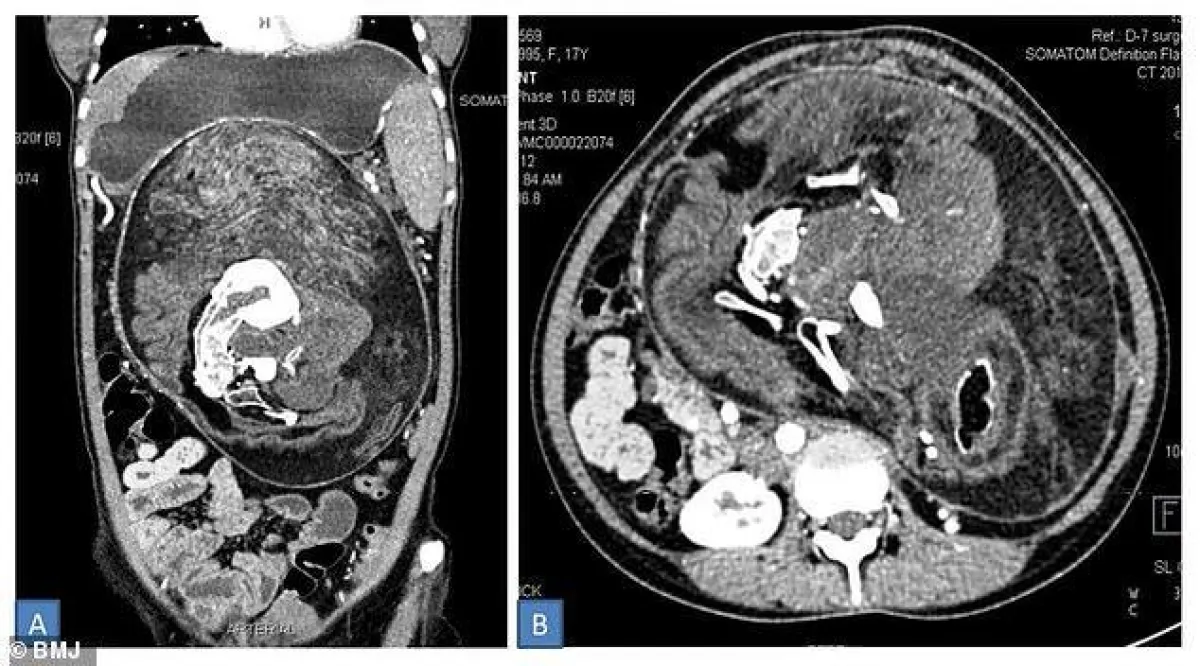

وتبين من خلال الأشعة التي أجرتها الفتاة وجود مجموعة كاملة من الأنسجة الرخوة ورواسب من الكالسيوم وبعض العظام وشعر وعدة أسنان وقد تمت إزالة الكتلة جراحيا.

وكان التوأم المشوه في جانب من الرحم وقد فشل في التطور وتسمى هذه الظاهرة بـ “جنين في الجنين” وغالبا يتم إجهاضه.